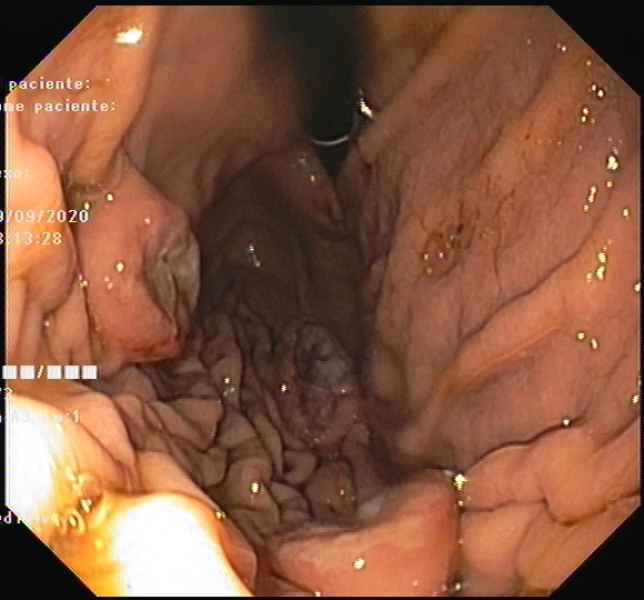

From IPMN to IPMN-derived invasive adenocarcinoma